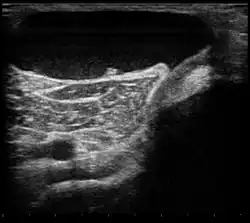

| Ultrasound image of Baker's cyst | |

Risk factors include other knee problems such as osteoarthritis, meniscal tears, or rheumatoid arthritis.[1][3][4] The underlying mechanism involves the flow of synovial fluid from the knee joint to the gastrocnemio-semimembranosus bursa, resulting in its expansion.[1] The diagnosis may be confirmed with ultrasound or magnetic resonance imaging (MRI).[3]

Diagnosis is by examination. A Baker's cyst is easier to see from behind with the patient standing with knees fully extended. It is most easily palpated (felt) with the knee partially flexed. Diagnosis is confirmed by ultrasonography, although if needed and there is no suspicion of a popliteal artery aneurysm then aspiration of synovial fluid from the cyst may be undertaken with care. An MRI image can reveal presence of a Baker's cyst.